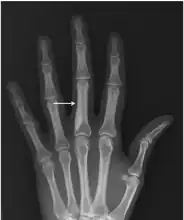

Osteopoikilosis

Note thickened sclerotic cortical bone